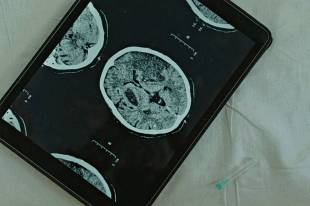

병원에서는 CT, MRI 같은 영상검사로 허혈성과 출혈성을 구분하고, 혈액검사와 심전도를 통해 원인을 찾습니다. 무엇보다 조기 치료를 위해 발병 시각을 정확히 전달하는 것이 필수이며, 이를 위해 가족들이 평소 응급 연락망을 정해 두는 것이 좋습니다.